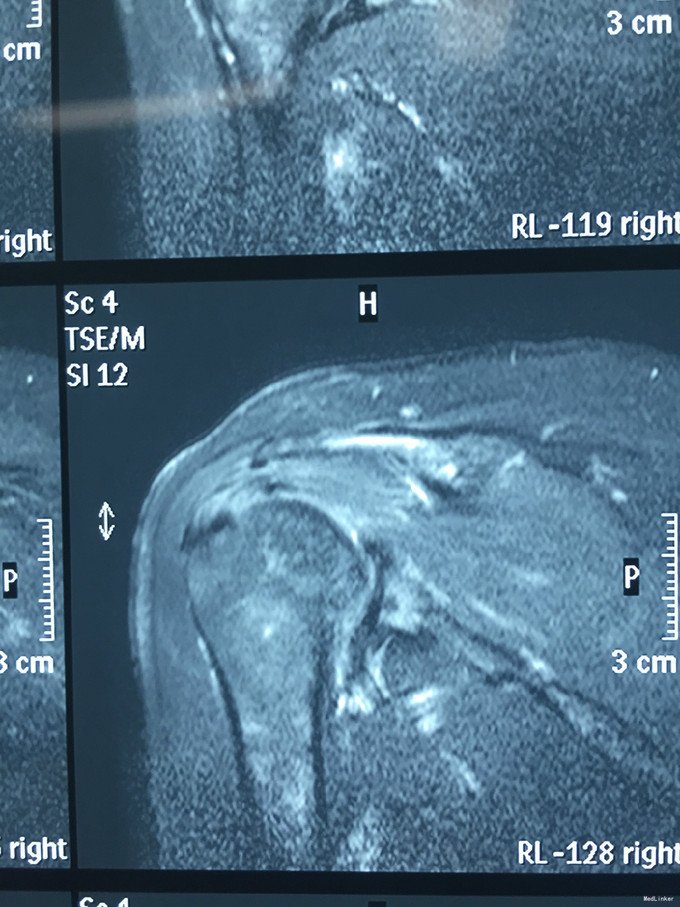

主诉:右肩疼痛5月,加重伴活动受限2月余。 现病史:患者,女性,45岁。5月前无明显诱因下出现右肩关节疼痛不适症状,偶伴有夜间痛,经休息等保守治疗后现疼痛症状略缓解。后患者至外院就诊,予口服药物等保守治疗,效果不佳,且有加重趋势。2月余前患者自觉右肩疼痛较前明显,伴活动受限。外院行MRI检查示:右肩关节内积液、右肩峰骨质增生、右肩袖肿胀、右肩盂唇信号异常。后患者来我院就诊,查右肩X线示:右肩峰前外侧见一骨性突起。门诊结合病史及体征,诊断“右肩峰下撞击综合症、右肩峰占位”收入院,行进一步治疗。

入院诊断:右肩峰下撞击综合症、右肩峰占位 治疗:右肩关节镜下肩峰成形,占位切除术

随访:患者术后感觉症状明显好转,肩关节活动度也较前改善。 讨论:该肿块性质尚无定论,仍需较长期的随访观察。请问各位专家,就目前的病史资料如何考虑该占位性质?